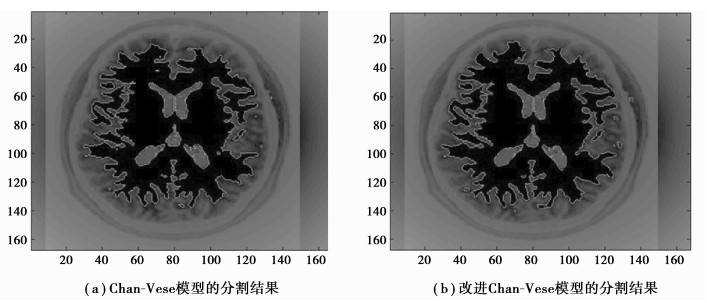

在验证实验中,选择了对比度较低、边缘异常不规则的图像(图 7),传统C-V模型的需要更多迭代次数,导致分割时间增加,而尖锐的边缘使其分割有效面积更小。改进的C-V模型则在一定程度上弥补了传统C-V模型算法分割的不足,如图 8所示。

|

图 8 两个分割算法对比 |

在第一组实验中,C-V模型耗时2.66 s,改进算法耗时2.03 s,有效面积增大率为3.5%;第二组实验中,C-V模型耗时3.87 s,改进算法耗时2.96 s,有效面积增大率为4.7%。实验表明:结合阈值算法的Chan-Vese模型图像分割方法提高了图像分割的准确性和快速性。

4 结语笔者利用阈值分割算法和C-V模型图像分割算法相结合的方式,充分发挥阈值分割方法简单快速和Chan-Vese模型自动化程度高,分割准确的优点,大大节省了算法分割图像时间的同时,有效优化了C-V模型处理复杂图像的能力,并通过实验验证了该方法的有效性和合理性,实现了预定目标,对临床医学具有实际的意义。